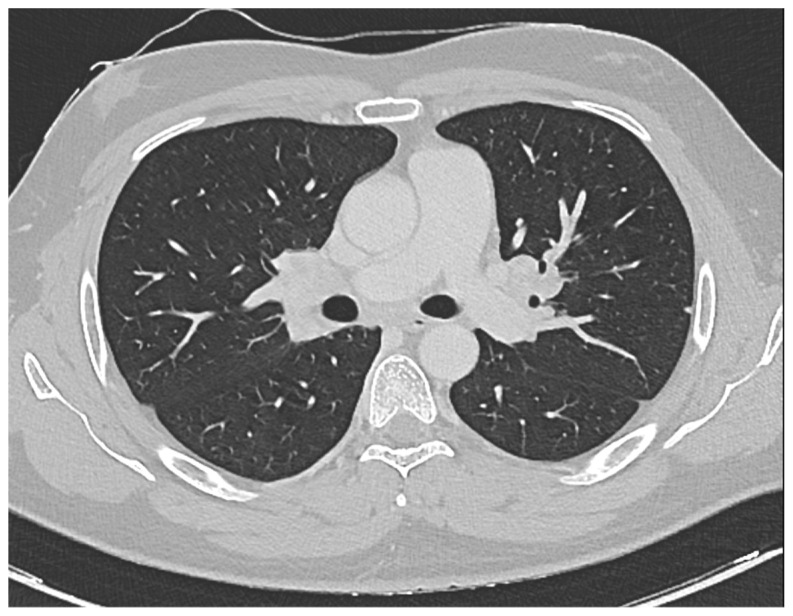

Sarcoidosis, a multi-organ system disease, often presents insidiously. Thrombocytopenia in sarcoidosis is frequent because of hypersplenism, granulomas infiltrating the bone marrow, or immune thrombocytopenia (ITP). The diagnosis of ITP relies on exclusionary criteria, given the absence of a definitive laboratory diagnostic feature. In the era prior to modern ITP management, sarcoidosis-associated ITP was known to manifest severely, often showing resistance to treatment and an increased risk of mortality. In this case, we present a young male who was admitted to a district hospital's emergency room, displaying symptoms of hematuria, gingival bleeding, and a petechial rash. Blood tests revealed severe thrombocytopenia with a platelet count of 0, while all other metabolic and serological exams returned normal results. Infectious and autoimmune causes were ruled out, and a bone marrow examination excluded any hematological disorder. Initial management, including platelet transfusion and presumptive treatment for ITP with dexamethasone and Human Immunoglobulin IV (IVIG), failed to improve the patient's platelet count or alleviate the hemorrhagic diathesis. Second-line therapy with Rituximab and Methylprednisolone was initiated with no benefit. Considering the hemorrhagic signs and the delayed response of Rituximab, we shifted to third-line therapy with Romiplostim at the maximal dose and continued Methylprednisolone. The platelet count recovered completely after the second Romiplostim administration (over 350 × 109 platelets/L) and Methylprednisolone was rapidly tapered. To further study the causes of thrombocytopenia a total body CT scan was performed and it identified non-homogeneously hypodense tissue in the bilateral hilar area extending medially to the subcarinal area, suggesting possible lymphatic origin and raising suspicion of sarcoidosis. Further investigations, including Angiotensin Converting Enzyme (ACE) titration, bronchoscopy, bronchoalveolar lavage, and EndoBronchial UltraSound-guided TransBronchial Needle Aspiration (EBUS-TBNA), confirmed the diagnosis of sarcoidosis. Despite a mild restrictive insufficiency noted in spirometry, the patient remained asymptomatic with only a mild respiratory insufficiency, and hence, was enlisted for follow-up. As for the ITP, the platelet count remained normal over a year. Notably, while sarcoidosis onset often predates ITP onset by an average of 48 months, in our case the onset of the two diseases was simultaneously. Our case adds valuable information to the limited body of knowledge regarding the treatment of sarcoidosis-associated ITP.